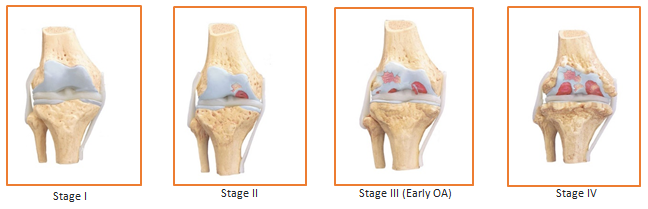

Stages of Cartilage Damage

- Stages I and II of cartilage damage are early stages. Once cartilage gets damaged, in its place fibrous cartilage (a very poor form of the actual cartilage – hyaline cartilage) is formed which has very poor mechanical strength.

- Presence of fibrous cartilage makes the joint susceptible to further injuries and it becomes very difficult to carry out normal activities like walking, running, yoga and sports. Reduced physical activity will lead to diseases associated with sedentary lifestyle such as diabetes, obesity, hypertension and cardiovascular disorders.

- A stage IV arthritic joint needs to be replaced by Total Knee Replacement Surgery.

- Cartilage does not have blood supply and will not heal on its own like a skin injury. Hence, cartilage damage needs to be treated by external intervention